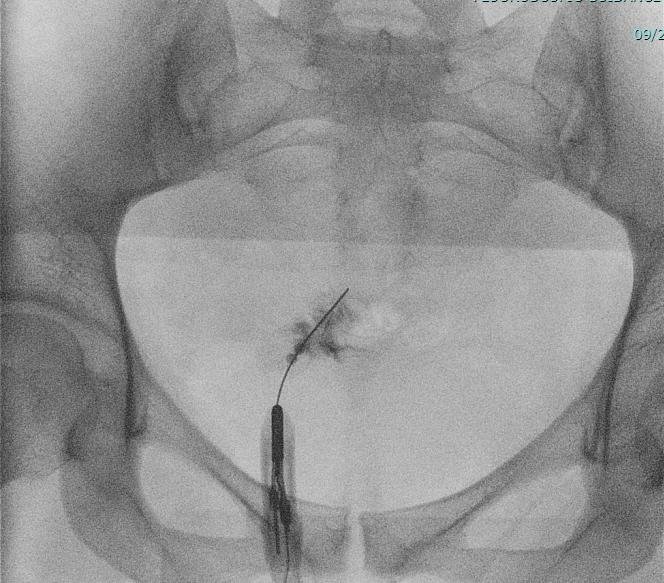

Minimally Invasive Pain Procedures

Cutting-edge treatments to improve patient comfort and recovery